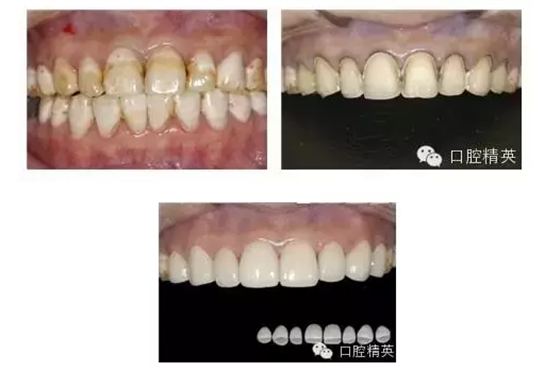

斑釉牙的修復。這是我們一個病例,牙的表面有一些,由于發(fā)熱的問題造成一些表面的礦化不全,出現(xiàn)了一些白斑,和一些表面的釉質(zhì)缺損,這樣我們就可以進行瓷貼面的修復,我們進行牙體預備以后的情況,可以看到這個表面的磨掉一層以后,正常這個牙體組織顏色而比較好的,所以通過我們修復以后,患者的牙齒顏色、外形都得到了一個很好的改變,功能上也沒有什么大的影響。這樣就是說給患者更多的自信心。